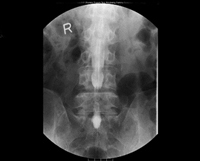

業務内容は胃がん検診が最も多く、その他にも大腸透視や脊髄造影、ERCP(内視鏡的逆行性胆管膵管造影)、イレウス管挿入、整復や気管支鏡生検など多岐に渡ります。